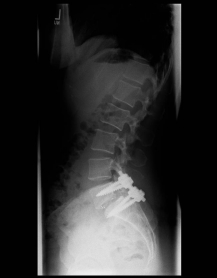

Spondylolisthese

X-ray image of a slipped vertebra in the lower lumbar spine before and after surgery